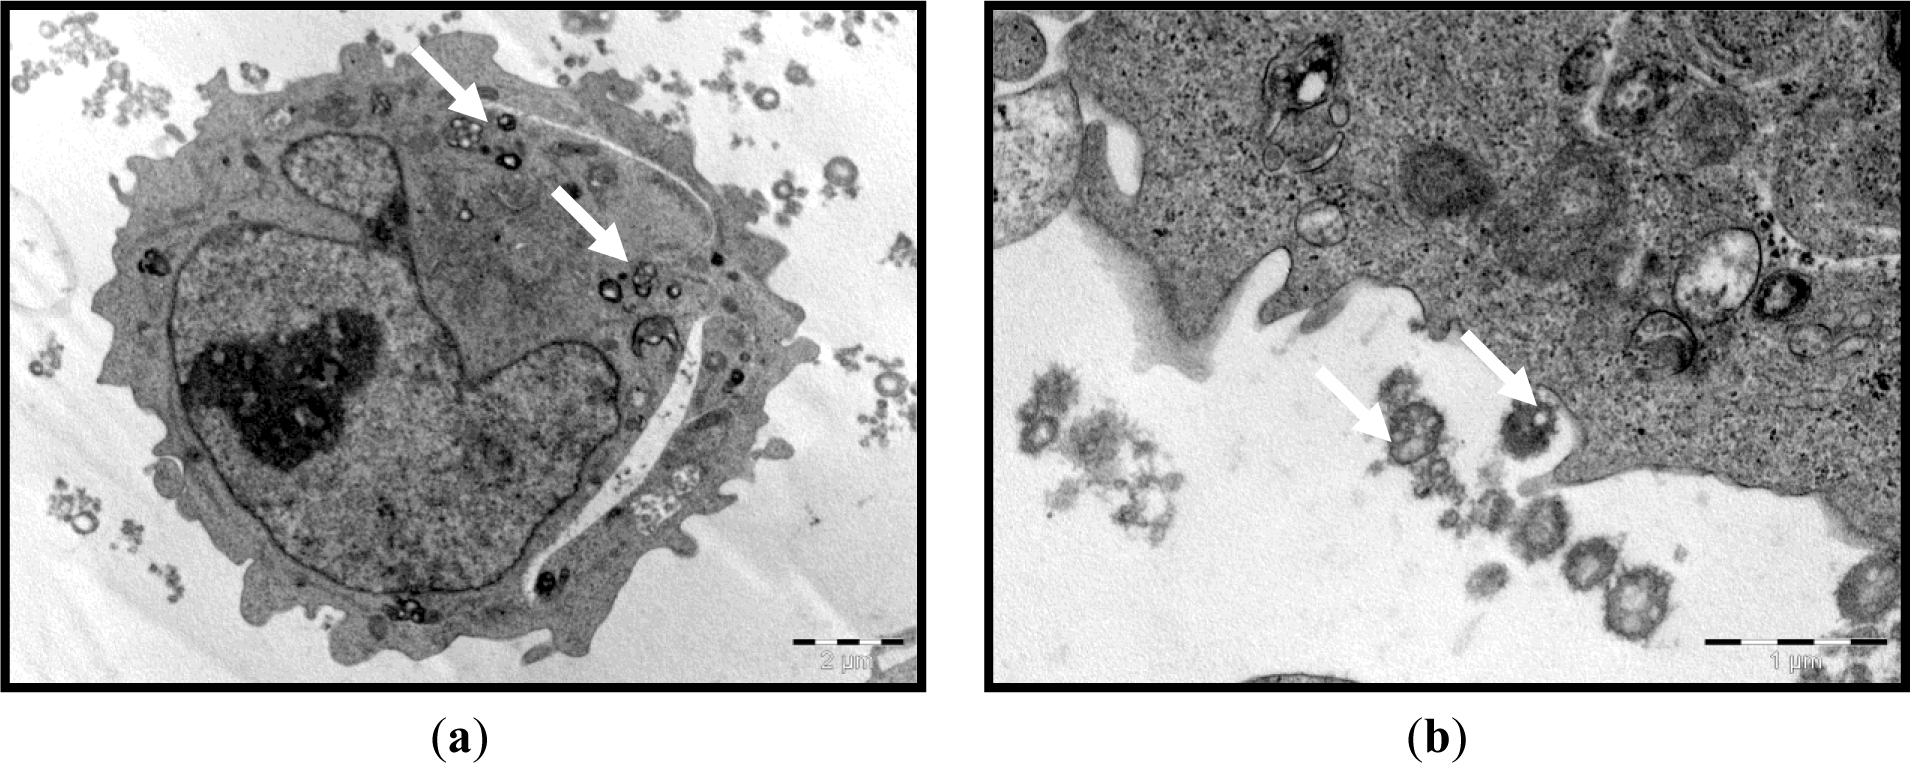

We first established that the characteristics of the prepared ENPs were an average size of 329.0 ± 18.5 nm and positive zeta potential values of 57.5 ± 5.47 mV. The prepared ENPs did not show any changes in their size in neutral or acidic conditions, indicating that no aggregation had occurred, except when serum was added to the media. The transmission electron microscope (TEM) images showed that the ENPs were nearly spherical in shape with a smooth surface (Figure 1). Moreover, in the in vitro study, the TEM observations revealed that the uptake of ENPs by THP-1 cell lines occurred after 2 h of incubation with a concentration of 200 μg ENP/mL (Figure 2a,b). The ENPs were observed in the cells after 24 h without inducing any changes in the cell structure (Figure 2c).

Zeta potentials provide quantitative information on the stability of the particles. In the current study, ENPs had an absolute value of zeta potential higher than 30 mV (+ 57.5 ± 50.7 mV). It is well documented that the particles are more likely to remain dispersed if the absolute value of zeta potential is higher than 30 mV [37]. The current results demonstrated that ENPs possessed a uniform shape along with relatively favorable dispersibility. The uptake was performed within the concentration range and time period, when no damage to cell viability confirmed the low cytotoxicity of the assayed polymeric ENPs to THP-1 cells (data not shown). This could lead to a true understanding of the relationship between particle size, as well as surface charge and cellular uptake. The THP-1 cells succeeded in inducing the uptake of ENPs (Figure 2). However, no difference was observed between the cells treated with a low or high dose of ENPs. On this concern, He et al. [38] reported that positively charged NPs showed a higher phagocytic uptake compared to negatively charged nanoparticles. However, Zauner et al. [39] suggested that the penetration of NPs into the cells might be attributed to the impairment of the cell membrane structure. It is well documented that the toxic effect of NPs is highly dependent on the organs and, more specifically, the type of cell encountered. This is due to the variation in cell physiology (e.g., epithelial or lymphoid), proliferation state (tumor or resting cells), membrane characteristics and phagocyte characteristics among different cell types [40]. The choice of the THP-1 cell line in the current study was based on the fact that these monocytes are the first line of innate immunity and, therefore, represent the first “barrier” or “target” of nanoparticulate delivery systems. On the other hand, the major objective of the current study was to investigate the effect of NPs on the hematological parameters, to assess the effect of the physical properties of ENPs on their toxicity and the possibility of NPs to penetrate the THP-1, as an example of blood cells.

4.4.2. Cellular Uptake Visualization by Transmission Electronic Microscopy (TEM)

Briefly, THP-1 cells were seeded in 6-well plates at a density of 3 × 105 cell/well and treated on the following day with 200 μg/mL of ENPs for 2 h or 24 h. Then, they were immediately fixed with ice-cold 2.5% glutaraldehyde for 2 h. Cells were then post-fixed in 1% OsO4 for 1 h at room temperature, progressively dehydrated by increasing concentrations of ethanol and, finally, treated with propylene oxide and included in resin. Semi-fine (2.0 μm) and ultra-fine (90 nm) sections were prepared with an ultra-microtome (Reichert-Yung) and examined with the electron microscope, Philips CM 12, operated at 80 kV.